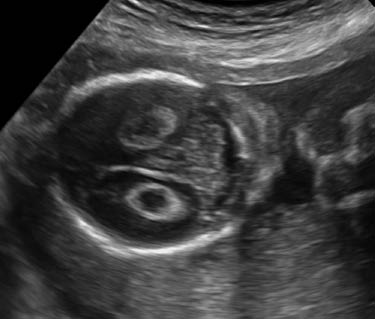

Choroid plexus cyst

Choriod plexus (CP) cysta are cysts that are seen within the substance of the choroid plexus. They can be single or multiple, unilateral or bilateral, and occur with an incidence of approximately 1%. They may result from entrapement of cerebral spinal fluid with tangled villi. As the stroma of decreases with increasing gestational age this fluid is relased and the the cyst resolves. For this reason more than 95% of these cysts resolve by the end of the second trimester [7].

The presence of a CP cyst has been associated with increased risk of trisomy 21, but even more so with trisomy 18 [8]. Seventy-one percent of trisomy 18 fetuses have CP cysts but these are usually associated with additional sonographic abnormalities [9]. The location, size, and morphology do not affect its relation to aneuploidy [9]. Isolated CP cysts create confusion, as its link to increased risk of chromosomal anomalies is less clear [9]. In a metaanalysis of more than 2000 cases with an isolated CP Cyst showed that trisomy 18 was found in one case out of 128 [10]. Based on the findings of this metaanalysis, the American College of Obstetricians and Gynecologists recommends offering amniocentesis in the case of an isolated CP cyst only if the age is >35 or with abnormal serum multiple marker screen [11]. Another large metaanalysis with 246,545 cases found 1346 cases of isolated CP cyst. The study concluded that only when a CP cyst was present with additional risk factors was an amniocentesis warrented [8].